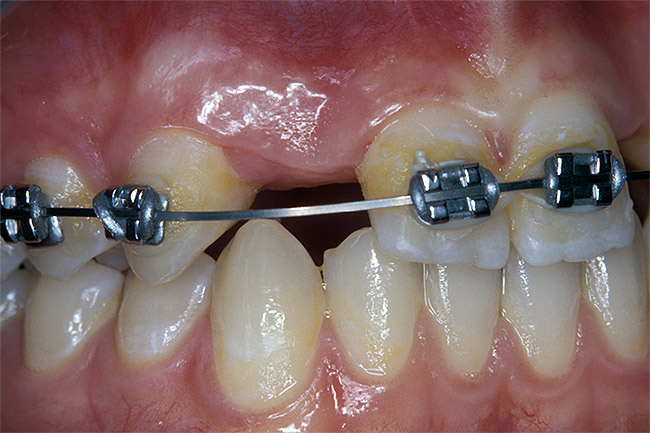

Before the day of surgery, the patient was seen by the orthodontist for the removal of the orthodontic brackets. The patient still was not pleased with the position of the two centrals, and it was determined that this would be addressed after implant placement (Figure 13A). The anatomical variations of the crestal tissue and lack of interdental papilla can be appreciated in the close-up views of the right and left sites (Figure 13B and 13C). There were no surprises on the day of surgery as all of the decisions were made during the planning phase, before the scalpel ever touched the patient. The occlusal view of the CT 3D model revealed the wider alveolar ridge on the right side and thinner crest on the left side (Figure 14A). This was confirmed when the full thickness mucoperiosteal flaps were elevated, and the underyling bone revealed (Figure 14B). The tooth-borne templates were designed to facilitate the drills and drilling sequence specific to the diameters of the predetermined implants (Figure 15A). Each template contained an embedded 5-mm long stainless steel tube, which was approximately 0.2-mm wider than each drill (just wide enough to allow for the drills to rotate freely). Once positioned over the natural teeth, the template was secure and offered precision accuracy in transferring the implant locations from the original software-designed plan, allowing the potential for internal and external irrigation (Figure 15B). The 3.7-mm diameter Tapered Screw-Vent implant drilling sequence requires three drills: pilot, intermediate, and final sizing. Thus, three separate templates were fabricated to a.commodate these sizes. The templates were removed easily and replaced with the next sequential size in less time than it takes to change the drill on the surgical handpiece. After the osteotomies had been.completed, the implants were delivered to the site (Figure 16A and Figure 16B). For this internal hex connection implant, the author r.commends that the flat of the antirotational hex be positioned to the facial for proper orientation of the restorative.components (Figure 17A). Preprepared margins were created from a milled titanium fixture mount transfer post, which was delivered to the implant as support for an immediate transitional restoration. The facial “dot” helped confirm the orientation of the abutment to the facially positioned flat side of the internal hex connection (Figure 17B). Before cementation of the transitional acrylic restorations, a closed-tray, fixture-level impression was made, and a soft-tissue model fabricated.

Figure 13b  Before implant surgery, the orthodontic brackets were removed, revealing (A) the position of the centrals, and (B, C) the anatomical variations of the crestal tissue and lack of interdental papilla.

Figure 13b

Figure 13c  Before implant surgery, the orthodontic brackets were removed, revealing (A) the position of the centrals, and (B, C) the anatomical variations of the crestal tissue and lack of interdental papilla.

Figure 13c